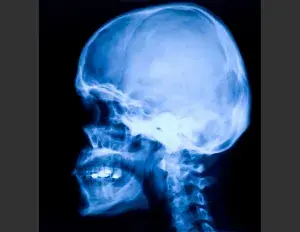

En segundo lugar, el sistema óseo desempeña un papel crucial en la protección de los órganos vitales. El cráneo, con sus placas duras y curvas, forma una caja protectora alrededor del cerebro, salvaguardándolo de impactos y lesiones externas. De manera similar, las costillas y el esternón envuelven y resguardan el corazón y los pulmones, mientras que la columna vertebral protege la médula espinal. Esta función de protección es fundamental para la supervivencia y el funcionamiento óptimo del cuerpo.

Cráneo:

El cráneo está compuesto por placas duras y curvas que envuelven y resguardan el cerebro, previniendo lesiones graves a este órgano esencial.

• Cráneo: El cráneo está formado por placas duras y curvas que envuelven y protegen el cerebro, evitando lesiones graves en este órgano vital.

• Cráneo: Ejemplo de un hueso plano que protege el cerebro y actúa como escudo protector.